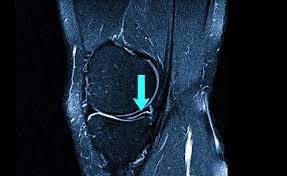

Для точної оцінки пошкоджень меніска на МРТ використовується класифікація Stoller, яка поділяє зміни на чотири ступені:

🔹 Stoller III

Сигнал доходить до поверхні меніска, що свідчить про наявність розриву.

МРТ колінного суглоба — основний метод візуалізації та класифікації